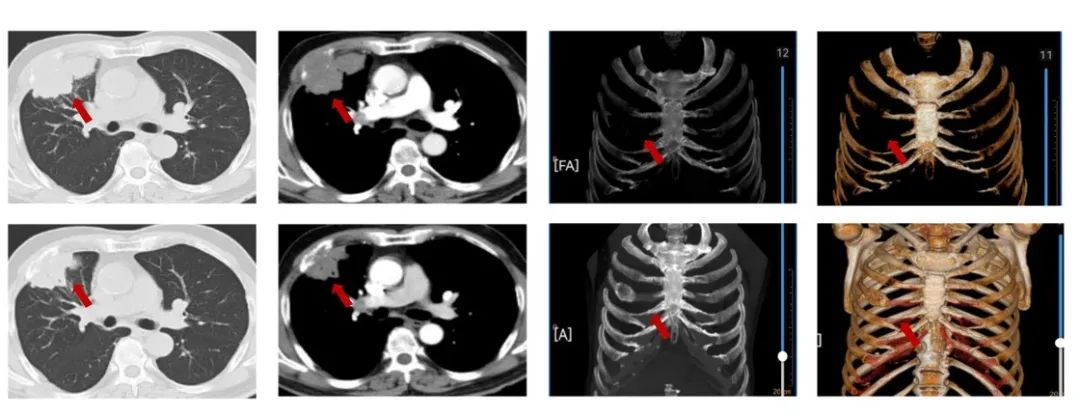

图1:由上至下分别展示基线(A.)及免疫化学治疗后改变(B.)。红色箭头指示病灶位置,由左至右分别为右肺肿物肺窗、右肺肿物纵隔窗、肋骨三维重建。